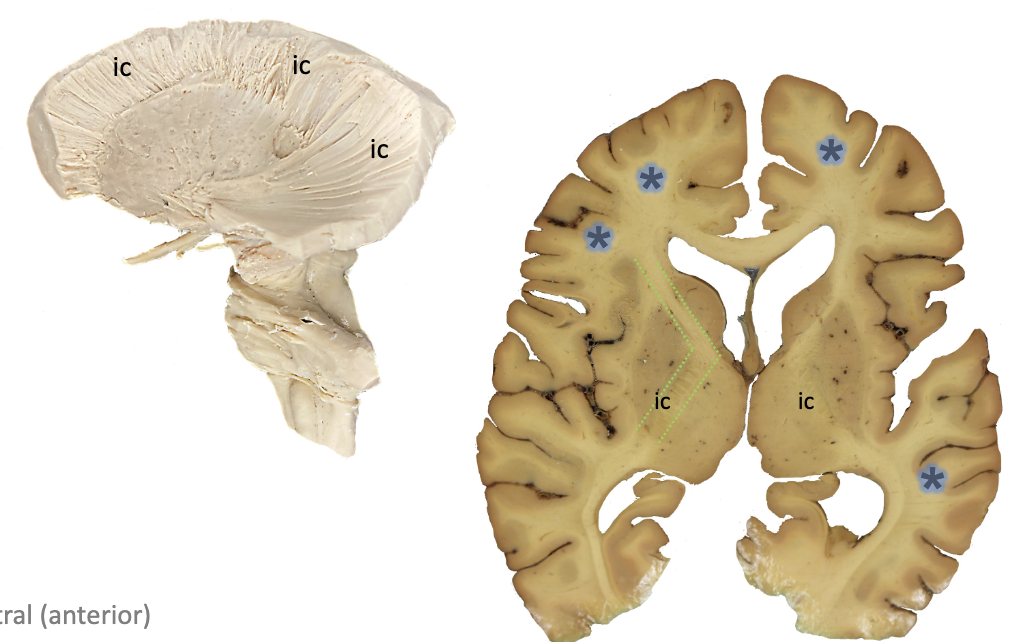

<p><strong>ic?</strong></p>

subcortical white matter

<p><strong>g?</strong></p>

genu

<p><strong>p?</strong></p>

posterior limb

• internal capsule

• _______: carries motor axons to trunk and extremities

• continues as the crus cerebri

• _____: carries fibers that go to brainstem

• ______ tracts: motor cortex to skeletal muscles of head and neck to coordinate precise, voluntary movements, travel in this area

posterior limb, genu, corticonuclear